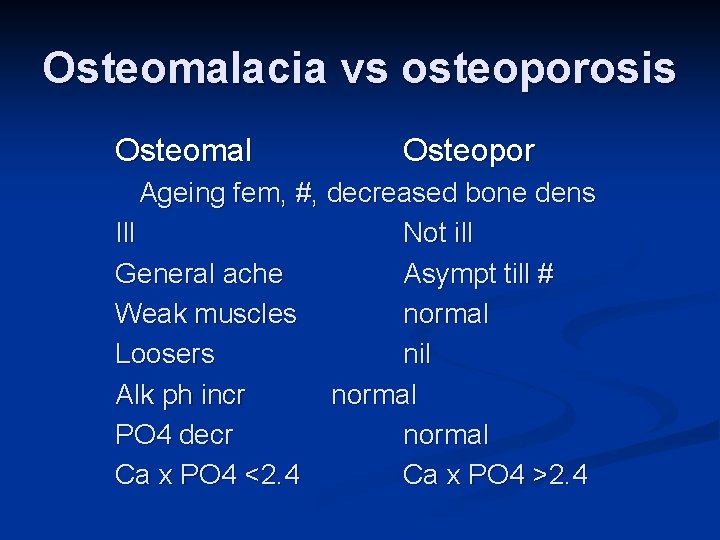

Osteomalacia vs osteoporosis Osteomal Osteopor Ageing fem, #, decreased bone dens Ill Not ill General ache Asympt till # Weak muscles normal Loosers nil Alk ph incr normal PO 4 decr normal Ca x PO 4 <2. 4 Ca x PO 4 >2. 4